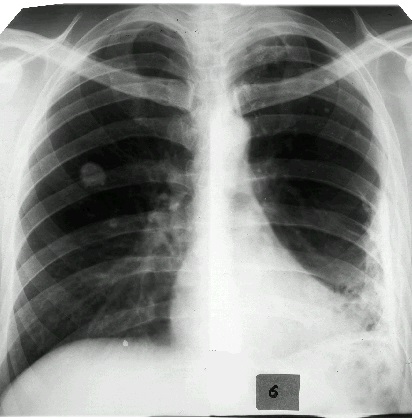

Плеврит может быть вызван большим количеством различных проблем. Первоначально, врач будет искать причину воспаления. Для этого он проведет обследование и выполнит рентгенографию грудной клетки. К возможным причинам плеврита могут относиться:

Пневмония.

Туберкулез.